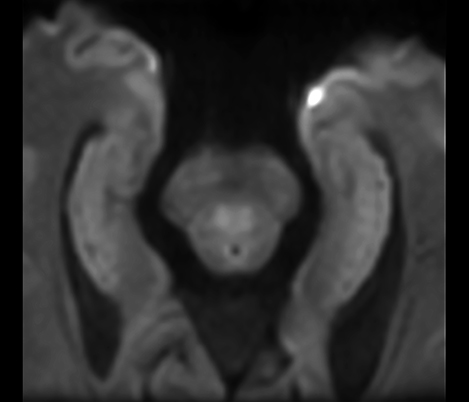

Casos clínicos de casi todas las anatomías Explore más de 100 casos clínicos de sus colegas en todo el mundo que muestran cómo la tecnología digital de resonancia magnética de Philips fortalece sus necesidades de imágenes.

Obtenga información sobre los antecedentes técnicos, las estrategias de optimización de protocolos, las dificultades de la imagenología y las direcciones futuras.